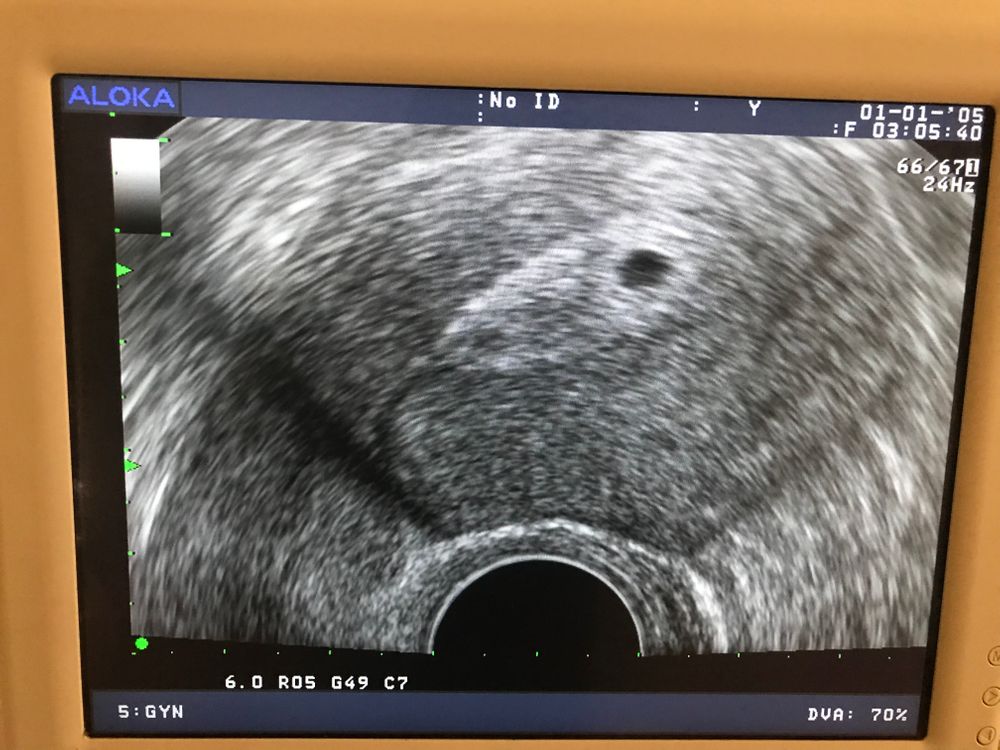

ПЯ 19мм

КТР 3,3

ЖМ 3.5

СБ -115

Эмбрион 1

Следующее узи 12н скрининг